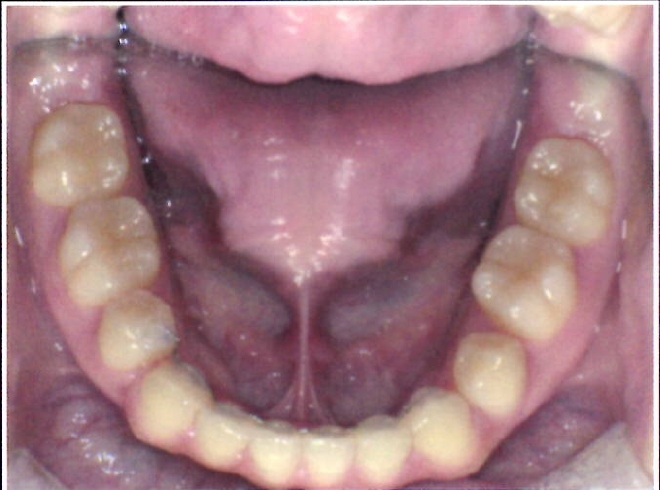

| 主訴・治療前の状態 | 下顎前歯部に叢生(ガタガタ)があり、歯ブラシが届きにくく清掃性に問題がありました。また、見た目も気にされていました。 |

| 治療内容 | 下顎前歯を1本のみ抜歯し、歯列を整えました。治療に際しては、ブラックトライアングル(歯と歯の間の歯茎部分に三角形の隙間ができること)が生じる可能性について事前に説明し、患者様にご了承いただいた上で治療を開始しました。 |

| 治療結果 | 予定通りの仕上がりとなり、事前説明の通りブラックトライアングルは生じましたが、患者様には十分ご理解いただいており、満足度の高い結果となりました。 |